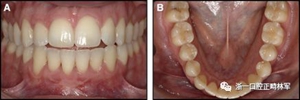

臨床檢查顯示固定保持器完好,弓絲沒有斷裂(圖13)。在下頜右側中切牙唇側和鄰近側切牙的舌側注意到有牙齦退縮。這些牙齒在退縮方向上存在顯著的扭矩差異。下頜的左側尖牙頰側錯位,而右側尖牙舌側傾斜。三維射線照片證實了下頜右側尖牙面?zhèn)妊啦酃菃适?,右側中切牙的喪失程度較輕。右側側切牙根也從舌側骨面上扭轉出來(圖14)。

圖13.粘合到尖牙和切牙上的柔性螺旋弓絲保持器,伴有牙齦退縮和附著喪失,中切牙之間嚴重的扭矩差異以及兩顆尖牙的橫向移動和扭矩。牙周問題和牙齒移動的嚴重程度均為牙周正畸聯(lián)合治療的指征:A,正面視圖; B,咬合面視圖。